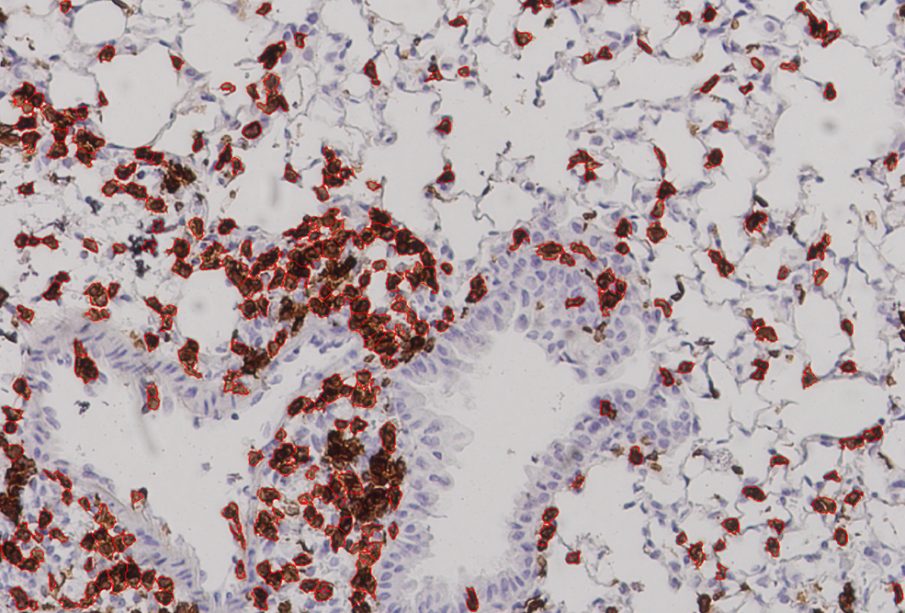

While that touches on the theoretical end of this project, the latest results came from experiments carried out by collaborators at the University of Texas Medical Branch in Galveston, which showed a strong immune response in mice given the vaccine. The mice in this experiment did not die but were were “humanized,” meaning that they had an HLA molecule found in human cells. “This study,” Carter says, “offers proof in a living system, an actual mouse, that the vaccines we devised using machine learning can afford protection from the Covid virus.” Gifford characterizes their work as “the first experimental evidence that a vaccine formulated in this fashion would be effective.”

More animal studies — and eventual human studies — would have to be done before this work can usher in the “next generation of vaccines.” The fact that 24 percent of the lung cells in vaccinated mice were T cells, Gifford says, “showed that their immune systems were poised to fight viral infection.” But one has to be careful to avoid too strong of an immune response, he cautions, so as not to cause lung damage.